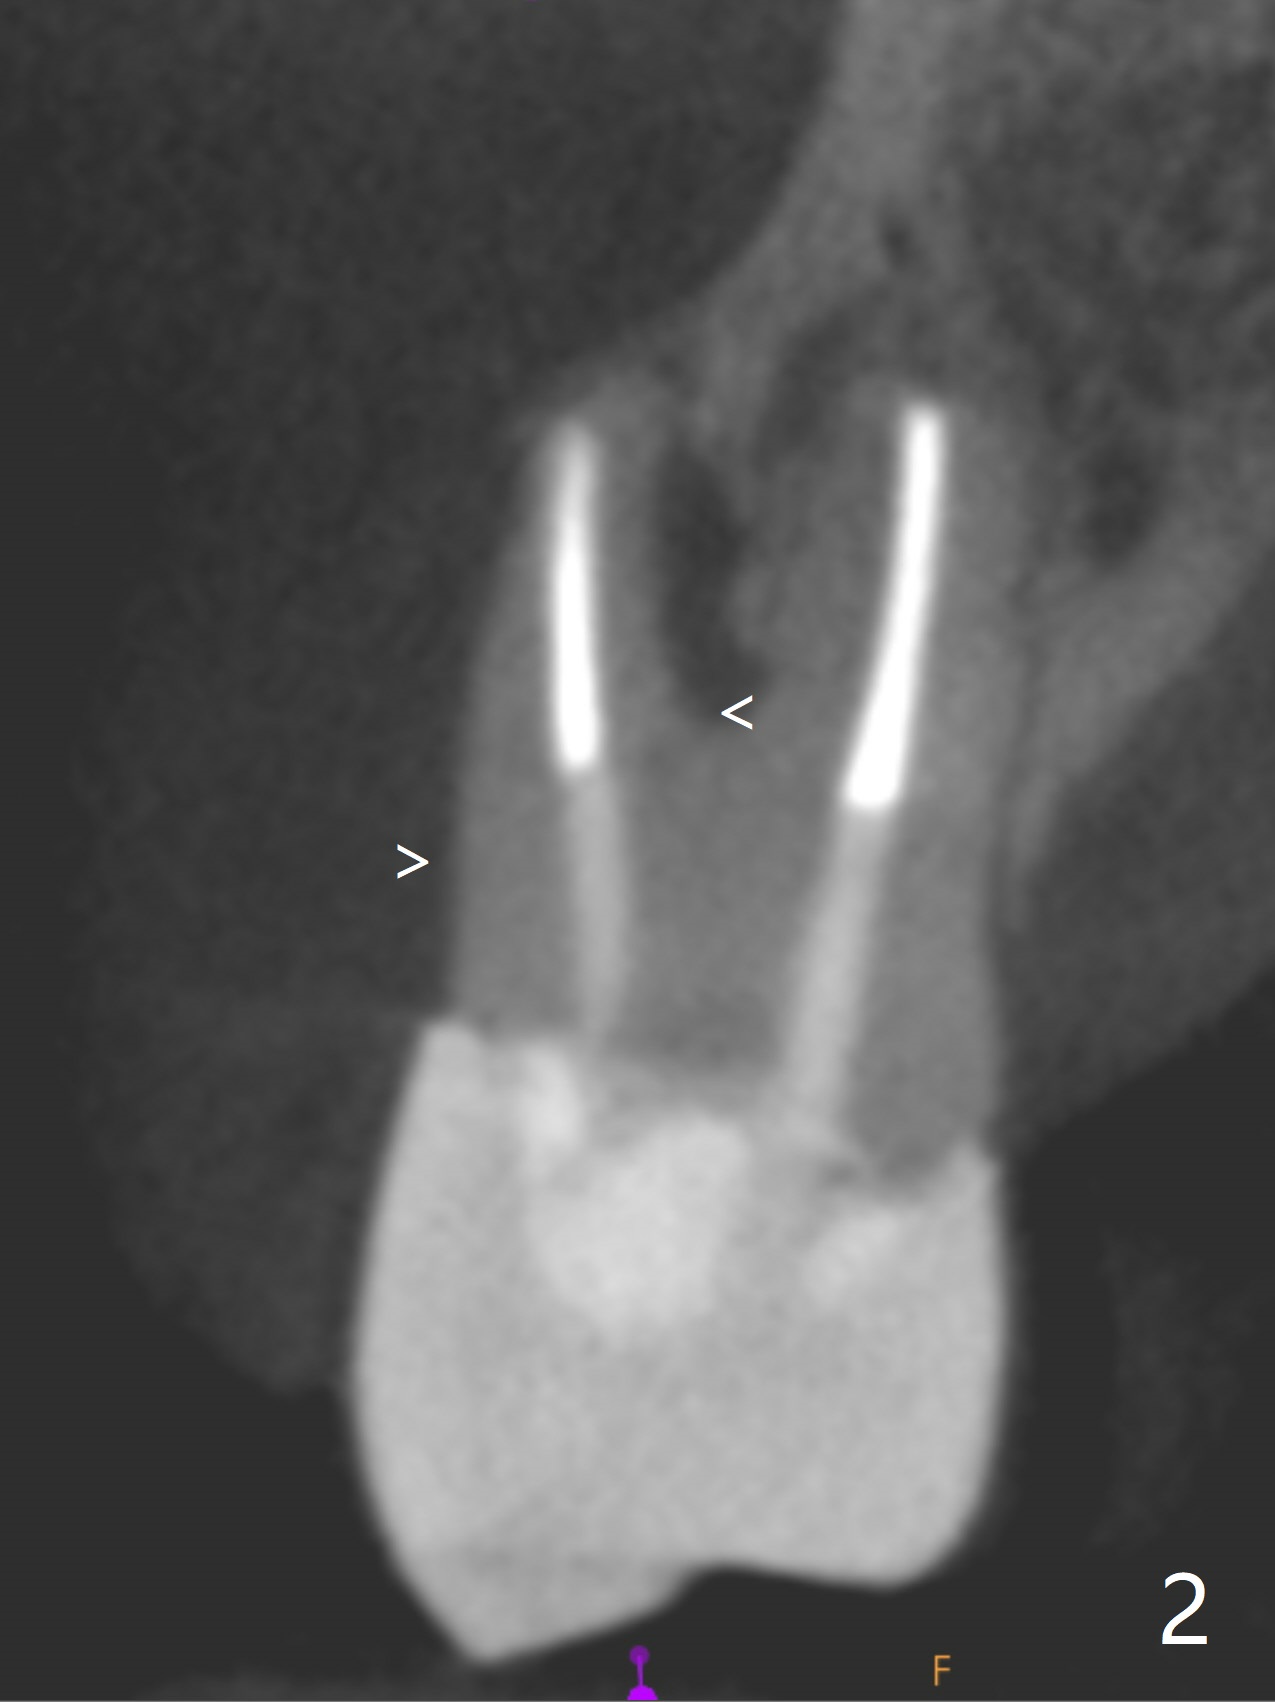

A 71-year-old woman with RPDs develops a fistula buccal to the tooth #5 (Fig.1). The buccal root seems to be fractured as indicated by arrowheads in Fig.2,3 (coronal and sagittal sections). The diagnosis of the fracture is confirmed by the abrupt change in density shown in Profile and the coronal section in Fig.4. Three-dimensional image demonstrates bone over the root surface of the teeth 6 and 8 (Fig.5 *), as compared to no bone over the the buccal root of the tooth #5. Due to financial constraint, the buccala root amputation is proposed as a treatment option. Is it viable?